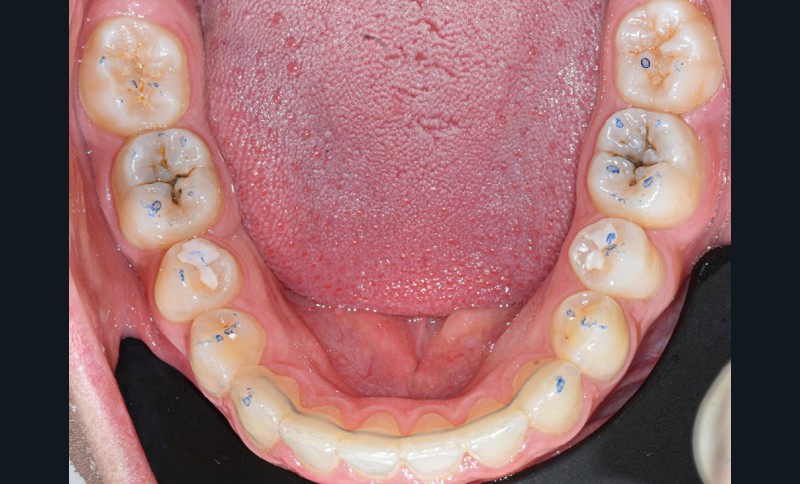

Nous détaillons la technique à travers le cas d’une jeune fille de 18 ans présentant des lésions carieuses sur quatre dents (fig. 1 à 14).